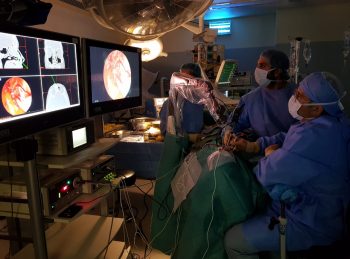

Minimal invazív sebészeti beavatkozások kiváló “asszisztense”

- Gyors, egyszerű üzembe helyezés

- Egy gombos pozicionálás

- Stabil kép minden pozícióban

- Kompatibilis minden standard endoscopos eszközzel

- VATS, kardiológia, Fül-orr-gégészet, idegsebészet